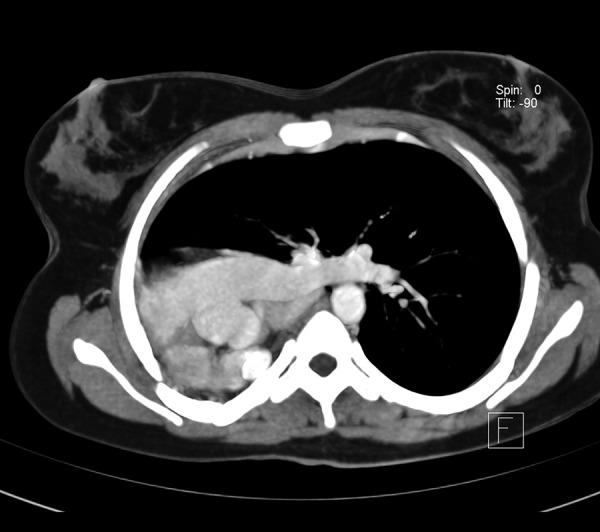

A young female, aged 15 years, presented with complaints of sore throat and cough. Her x-ray of the chest showed a homogeneous opacity in the middle and lower zones on the right side with marked shift of the mediastinum to the right side. Upon investigation, she was diagnosed with agenesis of the right lung with scoliosis, without any other congenital anomaly.

Especially in adults, it requires a high level of good clinical judgement to identify and diagnose this congenital aberration, as they are often wrongly diagnosed as more common diseases associated with unilateral opaque hemithorax on x-ray. Hence, when confronted with an opaque hemithorax with shift of the mediastinum to the affected side in a young person, "agenesis of the lung" should be an important differential diagnosis while investigating the case.